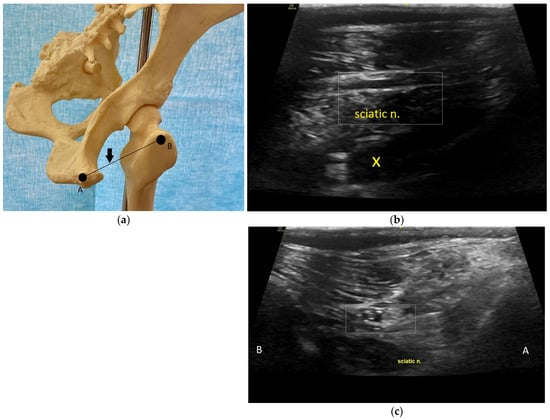

8.3. Tibial and Common Peroneal Nerve